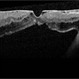

- vitreoschitic membrane

- vitreoschisis, myopic traction maculopathy

- intra operative photograph, SONY camera

- Triamcinolone enhanced visualization of vitreoschisis membrane and removal in a case of myopic traction maculopathy.